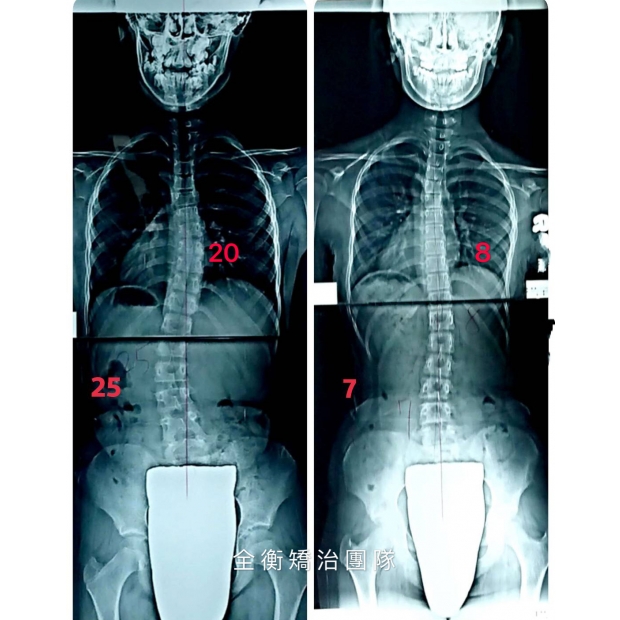

10歲脊椎側彎女孩 胸椎20度 腰椎25度

治療後追蹤胸椎減少至8度 腰椎減少至7度